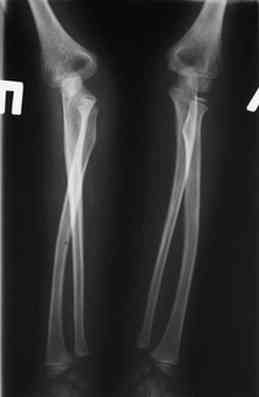

оперировали подобный случай около 6 мес назад. Отличие только в одном- давность травмы была до 2х лет. Использовали методику описанную в "Pediatric fractures and dislocations" Lutz von Laer, M.D.

Артротомия, иссечение рубцов, остатков кольцевидной связки. На проксимальный отдел локтевой кости стержневой аппарат (рекомендуют

Compact II выпущеный Stryker Howmedica, но за неименеем...), остеотомия проксимального отдела локтевой кости, вправление головки лучевой кости, замыкание аппарата, проверка стабильности головки

лучевой кости в движении, ушивание без пластики кольцевидной связки.

Данную методику применили впервые. После артролиза очевидная нестабильность головки луча. После остеотомии локтевой, вправления и

стабилизации аппарата головка луча при движениях на месте. Первые впечатления- "Либо чудо,либо фокус" (с) :))